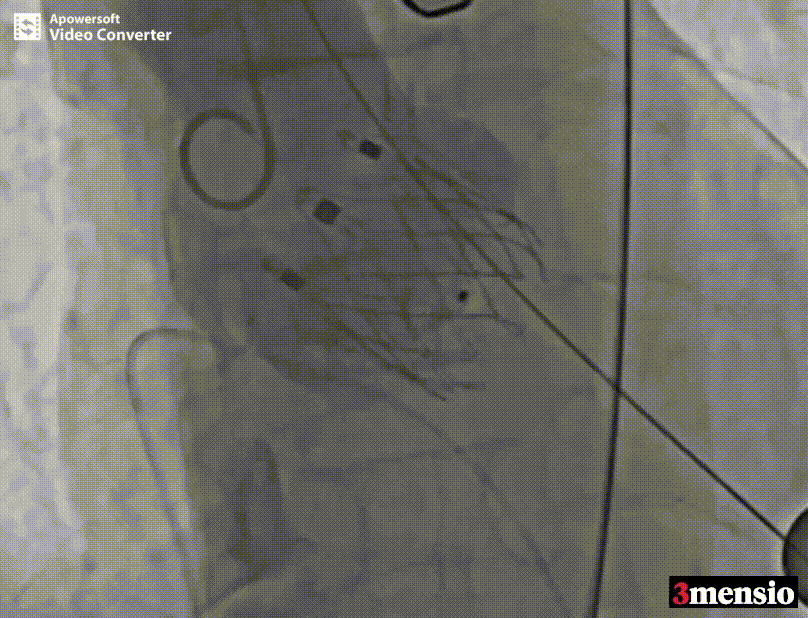

术中释放定位件造影图

瓣膜释放过程